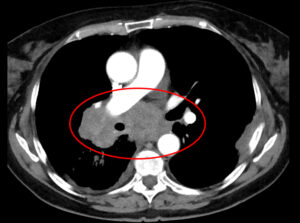

Aufnahme eines kleinzelligen Lungenkarzinoms, das zentral wächst und insbesondere den rechten Hauptbronchus einengt. - Auch in der Klinik für Allgemein-, Viszeral- und Thoraxchirurgie sieht Klinikdirektor Prof. Dr. Markus Rentsch vermehrt Patientinnen und Patienten mit schweren Krebserkrankungen des Magen-Darm-Traktes. Während des Lockdowns kamen vor allem bei potentiell heilbaren Tumoren der Bauchspeicheldrüse und Gallenwege, der Speiseröhre und des Dickdarms zwischen 20 und 30 Prozent weniger Patientinnen und Patienten. „Obwohl eine exakte Prozentangabe bei verschiedenen Tumorarten und individuell unterschiedlichen Grundvoraussetzungen problematisch ist, steht fest, dass mit jedem Monat, den der Krebs später erkannt wird, die Heilungschancen sinken“, betont Rentsch. Für viele der Erkrankungen, die in seiner Klinik behandelt werden, gebe es gute Früherkennungsprogramme wie etwa die Darmvorsorge.